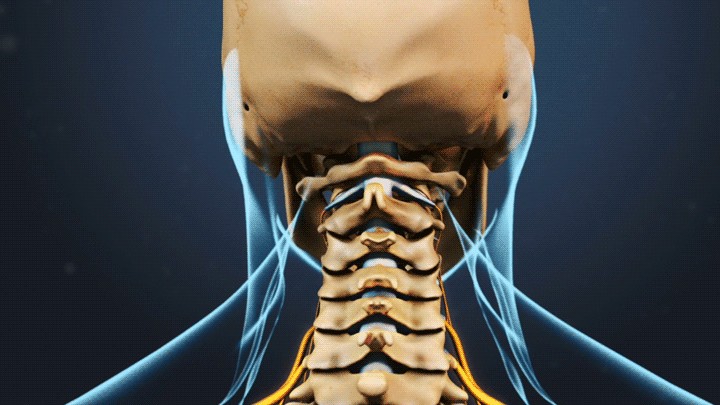

落枕,其实是颈部肌肉痉挛,常伴有颈椎小关节紊乱症状。

健康的颈椎有生理前屈,长期低头可使颈椎生理曲度变直甚至反弓,这部分患者更容易落枕。

若肌纤维多次受损,就会导致瘢痕修复,患者会感觉脖子在旋转时“咔咔”作响。长此以往,导致颈椎不稳,由筋到骨出现损伤,造成颈椎间盘突出、骨质增生、韧带钙化等后果。